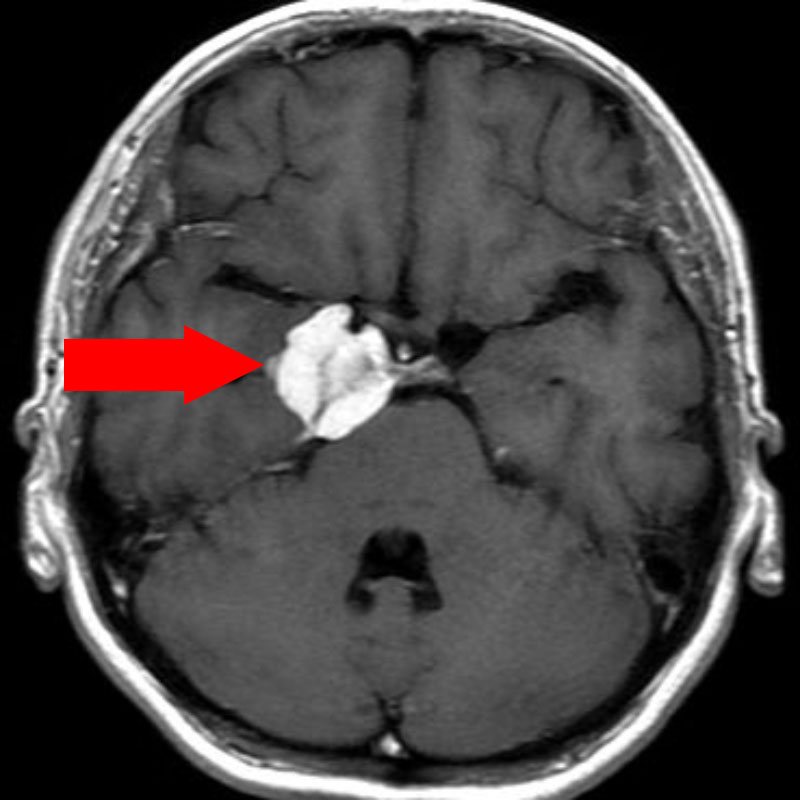

下垂体腫瘍

頭蓋内腫瘍摘出術

No.’22_98 手術前1

No.’22_98 手術前2